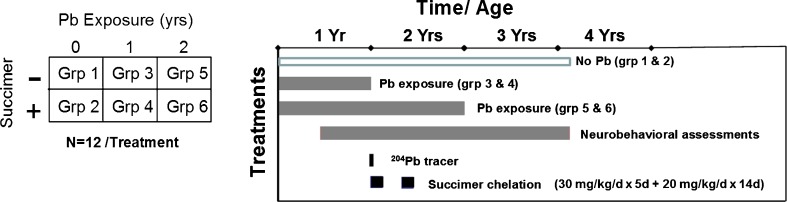

To address the first series of questions we will present results from a non-human primate study conducted several years ago [11]. This study utilized a 2 × 3 factorial design with two levels of succimer treatment (presence or absence) and three levels of lead exposure (no lead, daily lead exposure over the first year of life, lead exposure over the first 2 years of life). The animals were dosed orally with lead to achieve a target blood lead level of ∼40 to 45 mcg/dL. Animals were treated with a full chelation regimen (or vehicle) starting at 1 year of age (∼53 weeks) and again at age ∼65 weeks. The chelation regimen was comparable to that used clinically in lead-poisoned children; 30 mg succimer/kg/day divided into three daily doses for 5 days followed by a maintenance dose of 20 mg/kg/day divided into two daily doses for 2 weeks.

In addition, we utilized a stable lead isotope tracer methodology, in which animals were administered small amounts of stable 204Pb and/or 206Pb tracer prior to the start of chelation, in order to more precisely evaluate the movement and elimination of lead from the body with chelation. Animals were assessed with a battery of neurobehavioral tests spanning several years of testing. The general study design showing the timing and duration of lead exposure, chelation treatment, and neurobehavioral testing is shown in Fig. 1.

Fig. 1.

Study design and timing of testing in the primate lead chelation study (Smith et al. [11]). [Reprinted from Toxicology and Applied Pharmacology with permission from Elsevier]